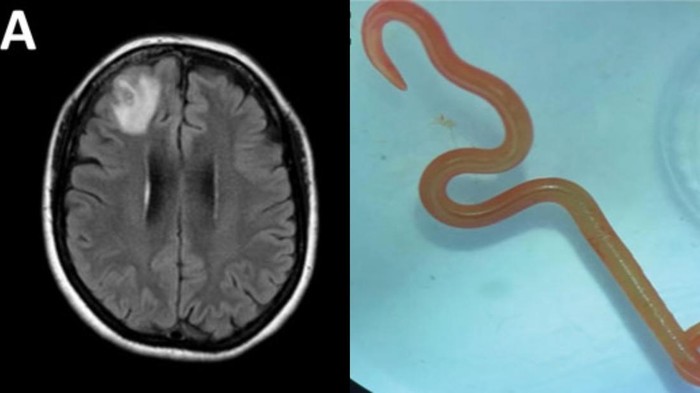

MRI otak kemudian mendeteksi adanya lesi atau kerusakan jaringan di lobus frontal kanan. Saat tim medis melakukan biopsi terbuka untuk memeriksa jaringan tersebut, mereka dikejutkan dengan penemuan struktur merah terang seperti benang yang masih bergerak di dalam otak pasien.

Berdasarkan temuan yang dipublikasikan oleh CDC Emerging Infectious Diseases, cacing tersebut diidentifikasi sebagai Ophidascaris robertsi. Yang membuat kasus ini sangat langka adalah fakta bahwa cacing parasit ini biasanya hanya ditemukan pada ular piton karpet (Morelia spilota).